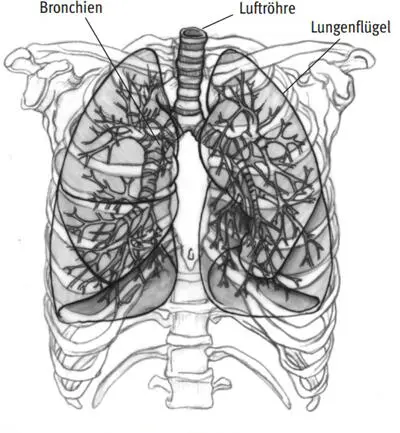

Der oben angesprochene Gasaustausch findet im Hauptatmungsorgan, der Lunge, statt, die sich im Brustkorb befindet (Abb. I.61). 8

Abb. I.61: Lunge, Bronchien und Luftröhre